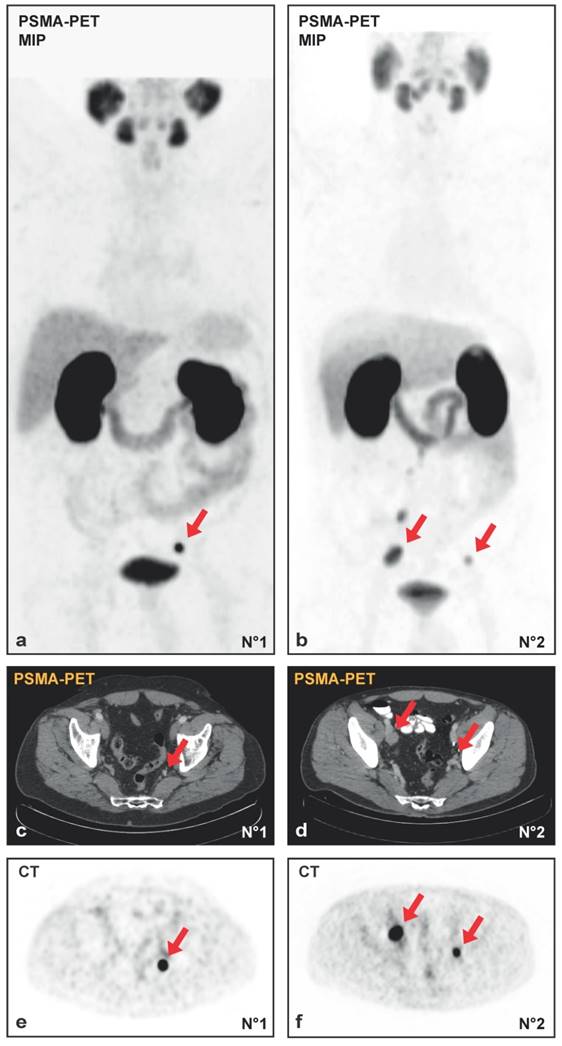

30 patients underwent template salvage-LND because of nodal PCa-relapse. 19/30 (63%) were in the high-risk group at primary diagnosis according to the D`Amico-classification. Based on the results of PSMA-PET/CT, all patients had the suspicion of at least one LNM. Complications arising from salvage-LND according to Clavien-Dindo were noticed in 16/30 cases (53.3%): 62% grade I (10/16), 0% grad II (0/16), 25% grade IIIa (4/16: lymphocele required secondary drainage) and 2% grade IIIb (2/16: renal congestion with ureter catheter insertion). No grade IV-V complications occurred. Representative maximum intensity projection (MIP) of two PSMA-PET/CTs and the corresponding PET and CT images prior to surgery are shown in Figure 1A-1F.

Figure 1

(A, B) Maximum intensity projections (MIP) of PSMA-PET/CT and the transversal PET (E, F) with the corresponding CT (C, D) images from patient N°1 with a single lymph node metastasis (initial PSA 7.43 ng/ml, Gleason-score 3+4 at radical prostatectomy in history, PSA 1.72 ng/ml at salvage-lymphadenectomy) and patient N°2 with multiple lymph node metastases (initial PSA 4.11 ng/ml, Gleason-score 4+5 at radical prostatectomy in history, PSA 1.78 ng/ml at salvage-lymphadenectomy). Red arrows indicate lymph node metastases.